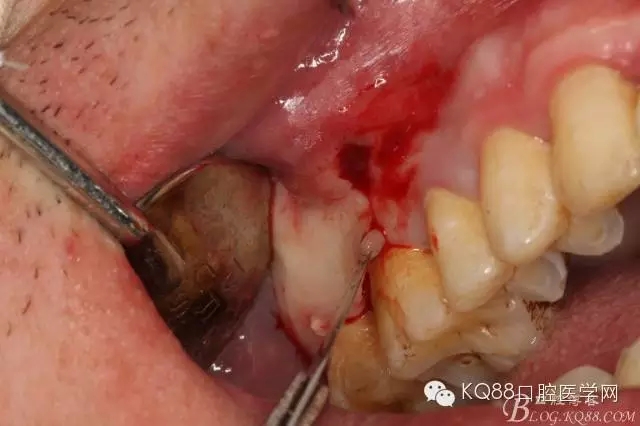

圖6.局部浸潤麻醉下。在16的近中做垂直切口+遠(yuǎn)中齦溝內(nèi)及上頜結(jié)節(jié)水平切口

圖7.翻全厚瓣。發(fā)現(xiàn)17牙根方的骨質(zhì)破損,破損處有大量膿性血性分泌物溢出。

圖8.繼續(xù)翻瓣至上頜結(jié)節(jié)處,發(fā)現(xiàn)骨壁缺損有花生米大小,腔隙內(nèi)有大量肉芽組織。